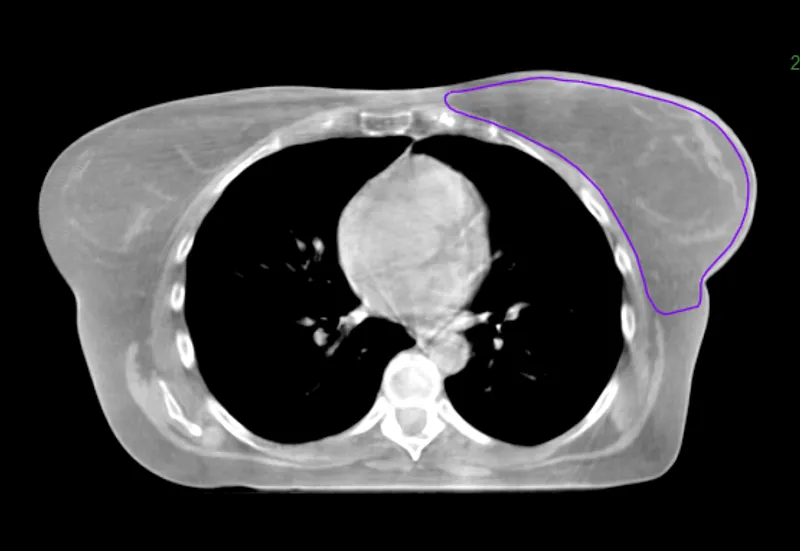

Breast

This HyperSight cone-beam CT for planning (CBCTp*) image, taken using a Varian Halcyon system,** encompasses the entire breast and body, giving clinicians the information they need to generate the initial treatment plan. During treatment, the larger FOV also enables clinicians to see and assess changes in adjacent anatomical structures and landmarks. If the change is deemed significant enough that offline adaptive is needed, they may be able to replan using the latest HyperSight CBCT image.

Hypersight breast and body

Image courtesy of Northeastern Oklahoma Cancer Institute, Claremore, Oklahoma.

*CBCTp is an image-only workflow only available on the Halcyon system.

**HyperSight on Halcyon has different specifications than HyperSight on TrueBeam, as the system configuration for Halcyon allows for a larger kV imaging panel.